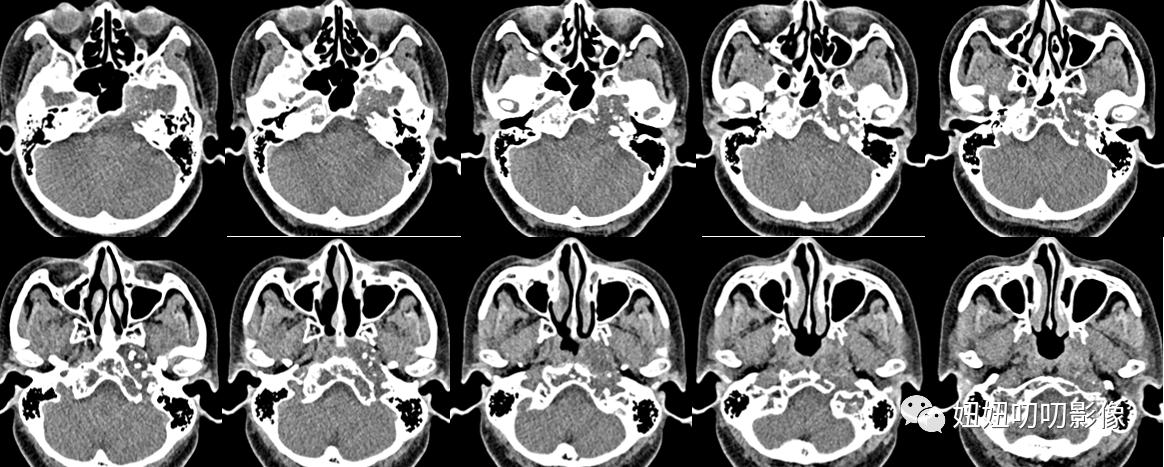

CT:鞍区及左侧岩尖区见不规则形等低密度灶,其内密度不均,可见斑点状致密影,斜坡、海绵窦、颞骨岩部骨质破坏,边界欠清,大小3.6x3.7x4.4m,增强扫描呈轻度不均匀强化,脑桥前缘、垂体、视交叉、左侧颞叶受压移位,左侧颈内动脉、大脑中动脉受压、迂曲增宽。

CT:鞍区占位性病变,软骨肉瘤可能,与脊索瘤等鉴别,请结合病理学检查。